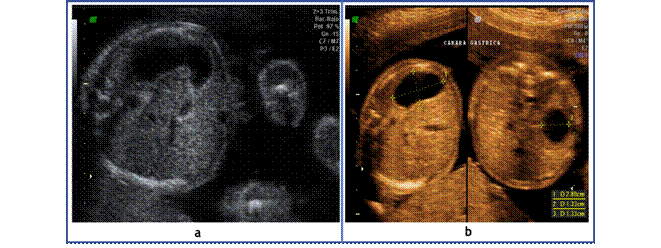

Llama la atención altura de fondo uterino discordante con la fecha de ultima menstruación que en este caso si es confiable, motivo por el que solicito ecografía obstétrica de control a las 22 semanas de gestación en donde se evidencio (Figuras 1,2 y 3).

Figura 2 (a y b). Ecografía obstétrica que indica dilatación de la cámara gástrica probablemente asociada a polihidramnios